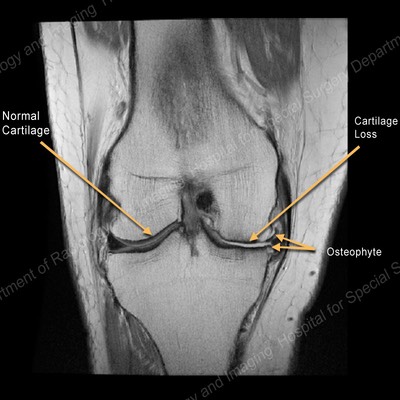

The Arthritic Knee

Arthritis causes a wearing out of the knee cartilage

Knee arthritis is a progressive wearing out of the normal articular cartliage that lines the moving surfaces of the knee. As the cartilage wears away it can become frayed and rough, and the thickness of the protective cartilage decreases. This wear and tear can be a slow and progressive process or can develop because of a prior injury. As the arthritic process progresses it can result in bone rubbing on bone, and become progressively more painful. The “environment” in an arthritic knee allows the “breaking down” (catabolic effect) process of the cartilage and meniscus to continue. The wear and tear cycle just continues until the knee is completely worn out.